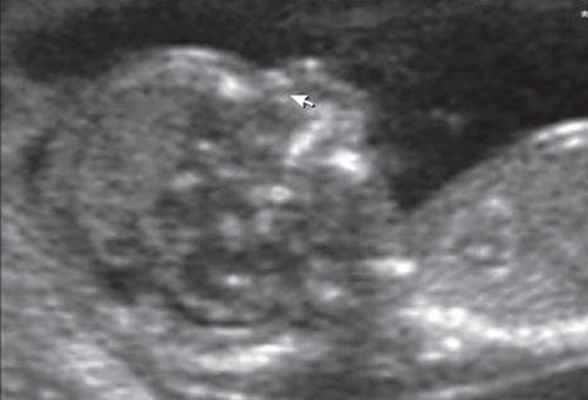

3D/4D объемная визуализация

Использование трехмерного ультразвука, включая визуализацию поверхности, многоплоскостное и многослойное изображение, позволяет точно оценить различные черепно-лицевые структуры и их аномалии, включая расщелину неба (рис. 15, 16) и краниосиностоз. Изображения могут быть полезны для консультирования (рис. 17, 18). Использование 3D (рис. 19) может помочь дифференцировать закрытые и открытые швы. Использование 4D может быть использовано для оценки выражений лица.

Рисунок 19: Плод во втором триместре с краниосиностозом.

3D поверхностное изображение в скелетном режиме, аксиального вида черепа показывает сужение (стрелки) венечного шва (CS) и части переднего родничка (AF).